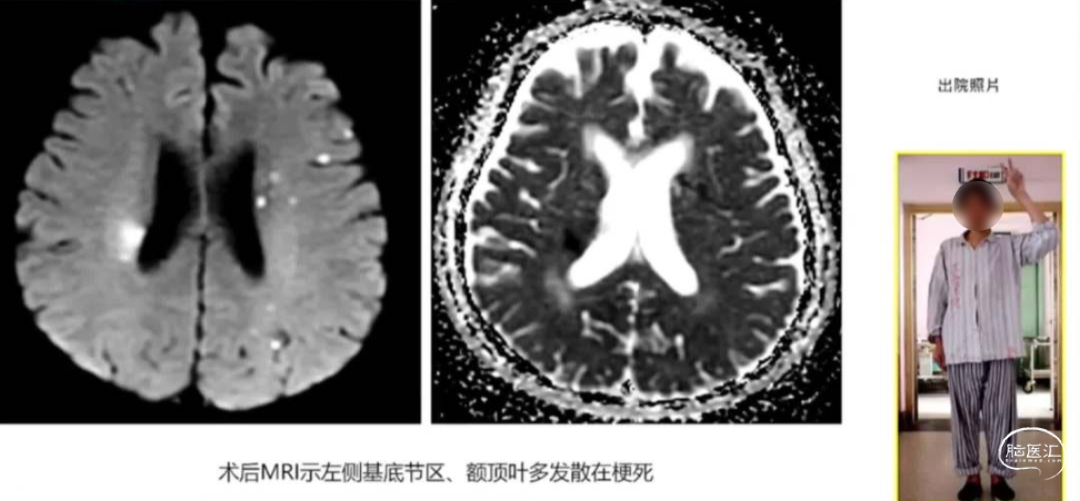

术后复查头颅MRI

同期治疗最大的优点是在最短的时间内化解狭窄和动脉瘤治疗中关于血流动力学改变而存在的潜在矛盾与风险。当然,对于该类病变是否应该进行同期处理,仍存在争议。相对于分期治疗,一次性治疗可能会发生更多出血、缺血并发症的几率。